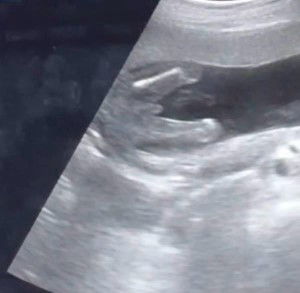

Gender @ 17 weeks

hi mommies! ano po sa tingin nyo gender ni baby, boy po ba? and accurate na po kaya? thank youuu ๐

yes boy po very proud๐ค

boy po